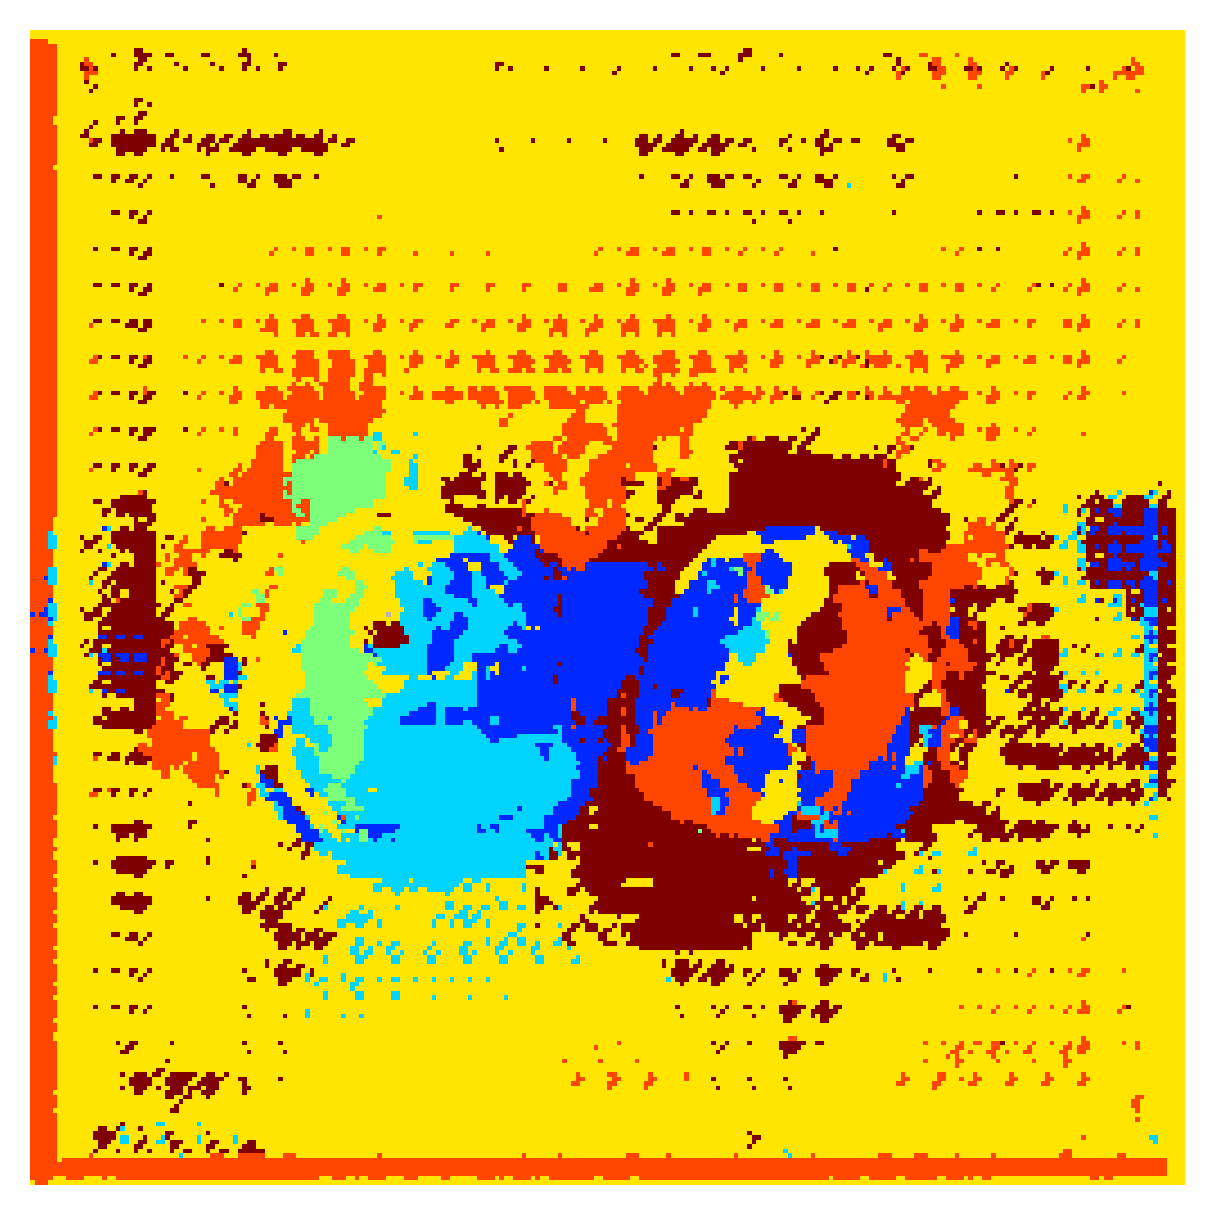

5.2.1 Qualitative comparison

In Figure 11 and 12 we show the same random slices in cases of calculating the boundary loss on 2D- and 3D-based distances, respectively. Comparing the two figures again indicates that the intensity-aware distances offer most improvement when calculated in 3D over 2D. The exception here is the MBD, which seems to even slightly degrade for most classes.